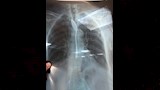

تمكّن فريق طبي بمستشفى شبين الكوم التعليمي في محافظة المنوفية، بقيادة الدكتور أحمد نبيل شهاب، من إنقاذ سيدة تبلغ 77 عامًا بعدما ابتلعت معلقة شاي في محاولة للانتحار، في واقعة تُعد الأولى من نوعها داخل المستشفى التعليمى.

وكان قسم الطوارئ بالمستشفى استقبل الحالة في تمام الساعة 7:30 مساء يوم الأحد الماضي، سيدة من مركز تلا، بعدما نقلها ذووها قائلين: "ألحقونا.. أمي بلعت معلقة"، موضحين أنها تعاني من اكتئاب مُمتد منذ خمس سنوات، وتتردد على مصحة متخصصة.

وباشر الفريق الطبي الفحص السريع وإجراء الأشعة اللازمة، ثم نجح في استخراج المعلقة باستخدام منظار طبي دون مضاعفات، وسط متابعة دقيقة للحالة حتى تحسنت وسمح لها بالخروج في اليوم نفسه، بعد أن رافقها سبعة من أفراد أسرتها.